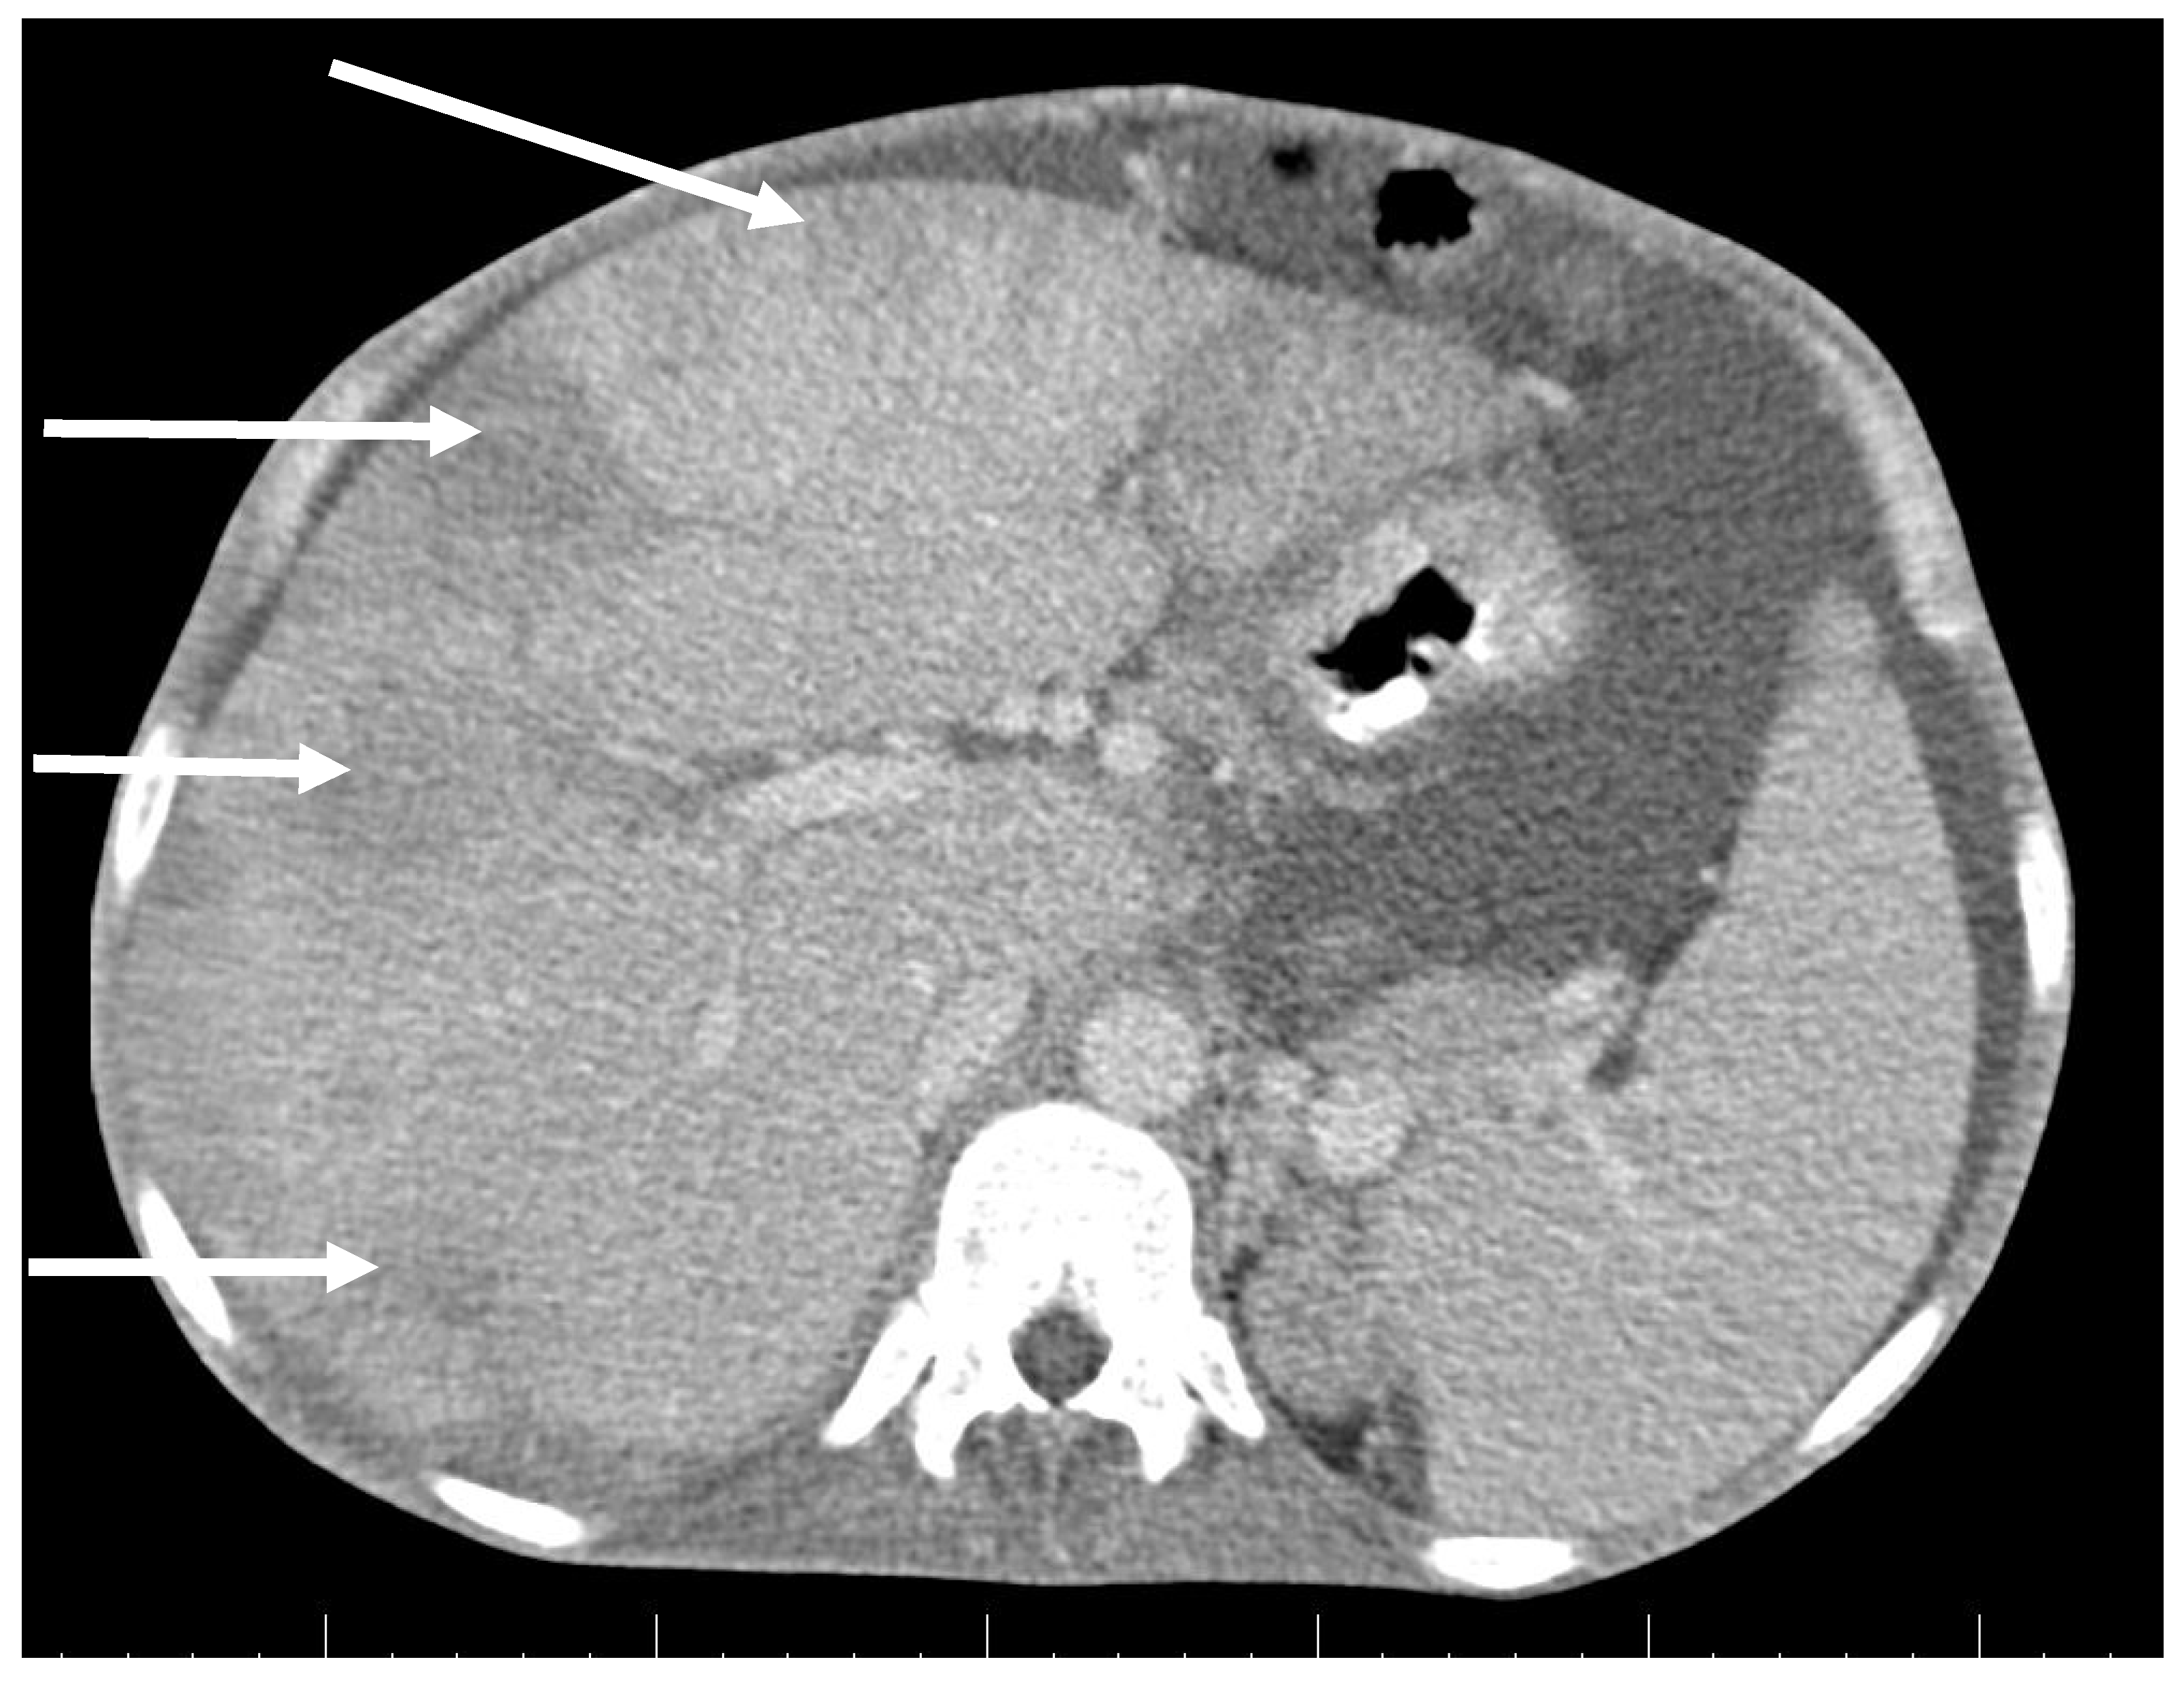

CT scan showed ascites, an enlarged right ovary with a parauterine non-homogenous mass 8 × 5 cm in size containing gas, bilateral hydronephrosis, ischaemic foci in spleen, multiple bilateral tiny nodules in the lungs with mainly subpleural distribution resembling miliary tuberculosis or multiple emboli, multiple liver lesions described as signs of Budd–Chiari’s syndrome due to the inferior vena cava thrombosis, and right hepatic vein thrombosis (Figure 1 and Figure 2).

Figure 2. Abdominal CT scan shows multiple lesions in the liver (arrows).